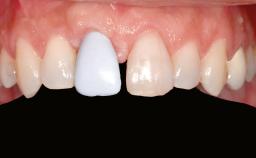

Prosthesis Type FDP

Defining Characteristics Up to three missing teeth to be replaced with an implant-borne restoration or restorations

Mesio-Distal Space Anatomic space corresponding to the missing teeth +/- 1 mm

Inter-Arch Distance > 8 mm